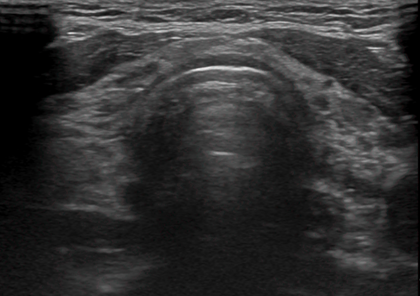

3) 초음파 검사

초음파를 이용해 뼈 밀도를 측정하는 방법으로, 일부 상황에서 사용됩니다.